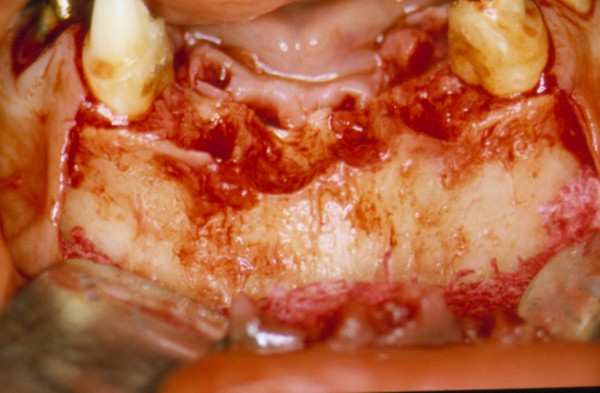

Sin más estudios, y convencidos del éxito del tratamiento, abordamos el mismo con las técnicas convencionales, y al realizar la periostotomía nos encontramos con un reborde acorde con los parámetros radiológicos.(DIAPO 3)

DIAPO 3